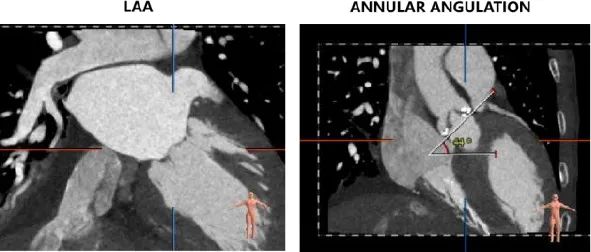

主动脉根部评估:

左冠开口高度12.0mm,右冠开口高度17.8mm,左冠高度较低,根据瓦氏窦内径和瓣叶长度综合判断,左冠存在较高堵塞风险;左室腔增大,心室壁未见明显增厚。

①患者左窦瓣叶明显长于左冠开口,窦部偏小,人工瓣膜打开后左冠闭塞风险较大大,需制定冠脉保护策略。

在术前评估阶段,首先通过心电图及超声探查,对患者心力储备、心脏电生理状况有了一个基本的把握,明确了患者自身的完全左束支传导阻滞,以及低 LVEF 情况。之后的 CTA 评估,通过瓣环上平面测量,提示了瓣叶较大冗长,上缘延展于 STJ 平面以上。于术前明确了冠脉极高闭塞风险,指示术中球囊预扩时,除常规 Balloon sizing 再次确认瓣膜型号外,还应当着重观察左冠灌注情况。